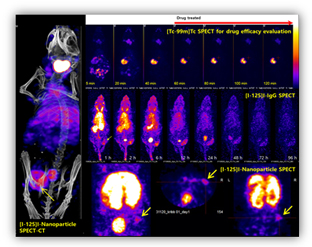

소동물 SPECT

- SPECT용 방사성의약품을 이용하여 체내에서 일어나는 생화학적 반응 및 질병을 진단하는 영상법

- 영상 장비 / 소프트웨어 : NanoSPECT (Bioscan) / 1 mm high resolution / InVivoScope software / Mouse & rat only

- SPECT 방사성의약품을 이용하여 체내에서 일어나는 생화학적 반응 및 질병을 진단하는 영상법

- 전임상에서의 약동학/약력학 (PK/PD) 연구 지원

- SUV(Standard Uptake Value) 값을 통한 정확한 병변내 방사성의약품의 섭취율 분석

- 대표적인 SPECT 방사성의약품

- [Tc-99m]MDP (뼈 영상), [Tc-99m]MAA (폐관류 영상),

[Tc-99m]Phytate (림프절 영상), [Tc-99m]DISIDA (간담

도 영상), [Tc-99m]MIBI (부갑상선 영상), [Tc-99m]DMSA

(신장 영상) 등

- [I-123]mIBG (신경내분비선종 영상), [I-125/I-131]NaI

(감상선암 영상 및 치료) 등